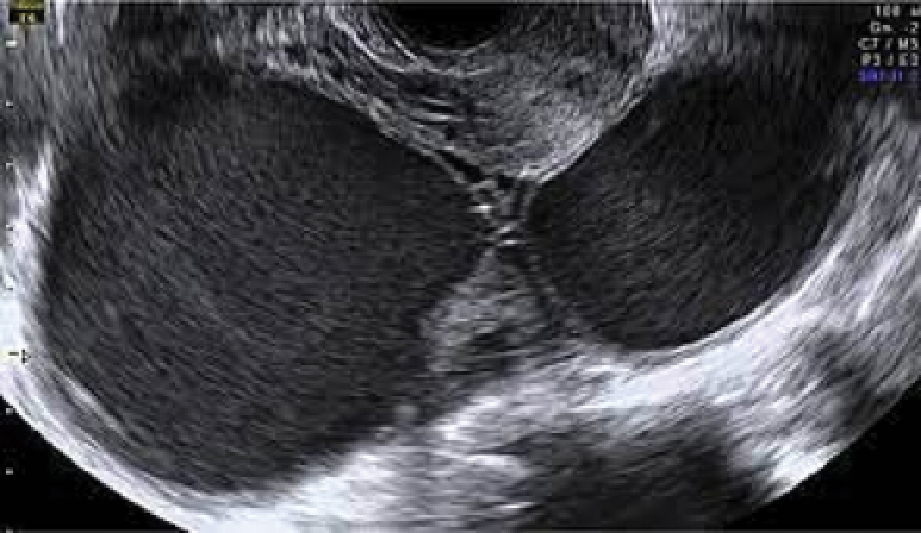

Magnetic resonance imaging (MRI). An MRI uses magnetic fields, not x-rays, to produce detailed images of the body. A special dye called a contrast medium is given into patient’s vein before the scan to create a clearer picture. MRIs create more detailed pictures than CT scans and are the preferred way to diagnose a brain tumour. The MRI may be of the brain, spinal cord, or both, depending on the type of tumour suspected and the likelihood that it will spread in the brain and spinal cord. There are different types of MRI, doctor will helps determine which type of MRI to use.